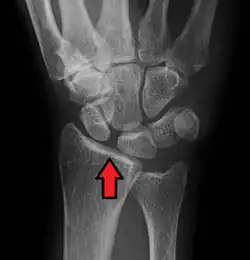

X-ray images indicate scapholunate ligament instability when the scapholunate distance is more than 3 mm, which is called scapholunate dissociation.[7] A static scapholunate instability is generally readily visible, but a dynamic scapholunate instability can only be seen radiographically in certain wrist positions or under certain loading conditions, such as when clenching the wrist, or loading the wrist in ulnar deviation.[6]

Static scapholunate dissociation -